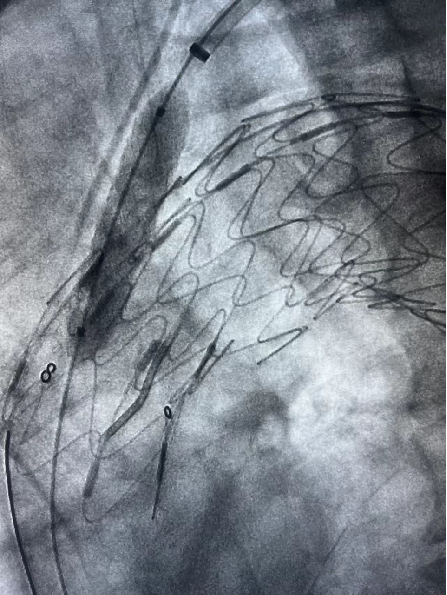

患者男性,51岁,主动脉夹层,通过Futhrough系统完成左锁骨下动脉(LSA)原位开窗重建。术中使用可调弯鞘(Fustar)和破膜系统,DSA显示破膜即刻成功,术后分支通畅,无并发症。

术前造影

穿刺破膜

球囊后扩

术后造影